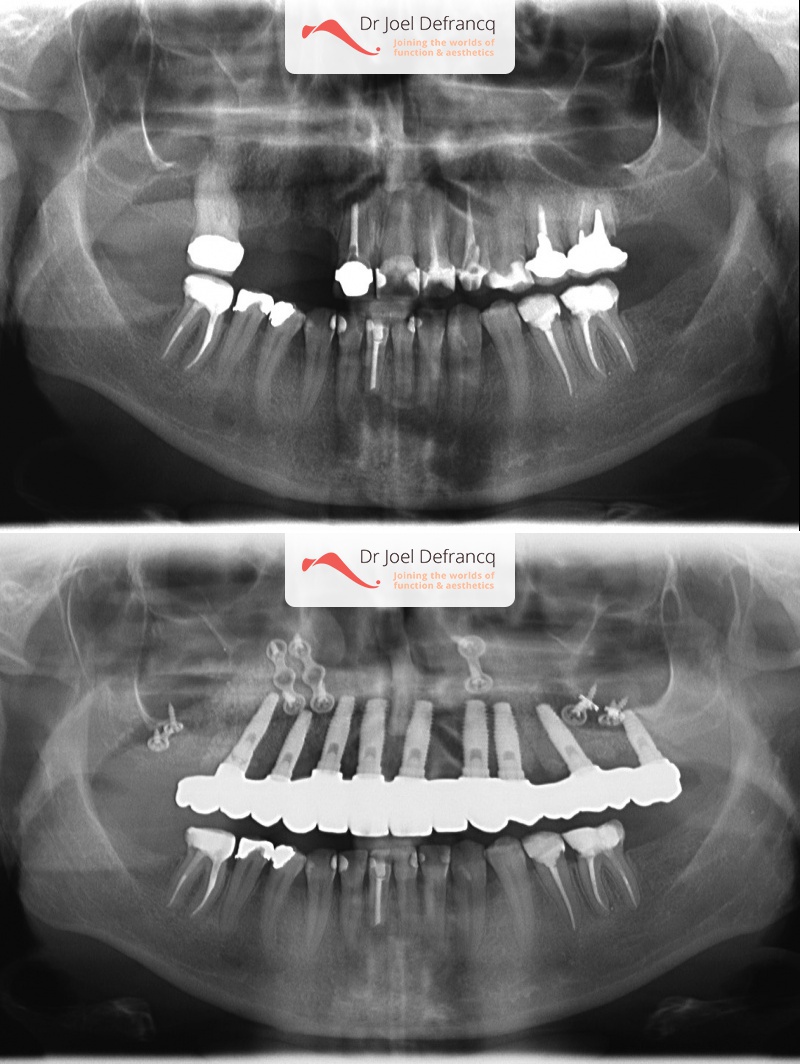

Vitali: upper jaw too far back - jaw surgery & implants.

Kaakchirurgie

- Verlenging bovenkaak (Le Fort I)

Behandeling tandheelkundige implantaten

- Vaste tanden op implantaten (bovenkaak)